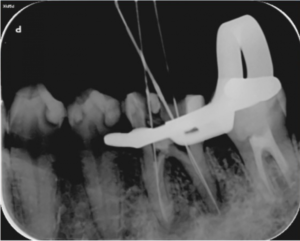

治療中

歯の根の治療中のレントゲン写真です。

歯の根の中を清掃する器具を入れています。根の中のばい菌を除去してきれいにしています。

歯の根の中を清掃し終わった後に内部に薬を詰めた直後のレントゲン写真です。

薬は根の中に緊密に詰まっています。一部先から漏れている部分もありますが、のちに吸収されていきます。